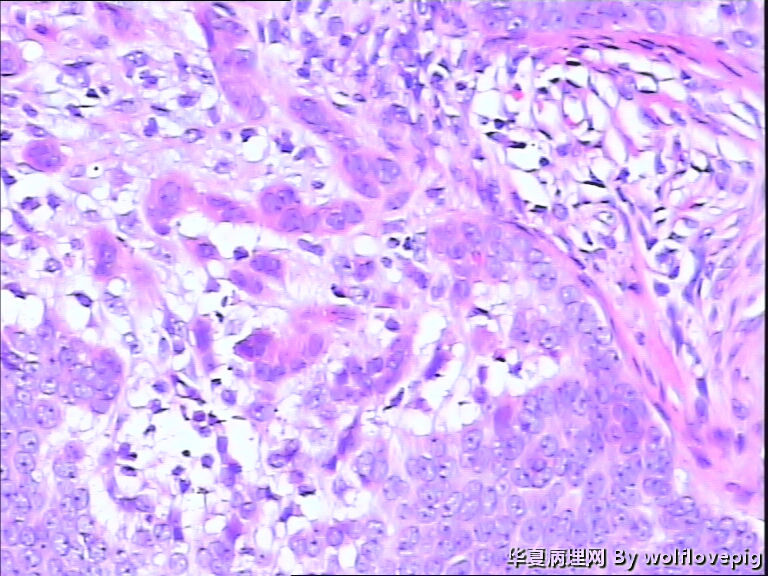

女,58y,右面部包块10年。灰白不整形带皮组织一块:2.3cm*1.5cm*0.3cm,切面有一灰白区域,质软,边界欠清。

诊断考虑毛母细胞瘤,或毛发上皮瘤。细胞团块周围可见嗜酸性纤维包绕,间质内纤维增生明显。

与表皮无关,表皮无破溃,无收缩间隙-------不支持BCC  有角囊肿 促纤维增生-----支持毛发上皮瘤